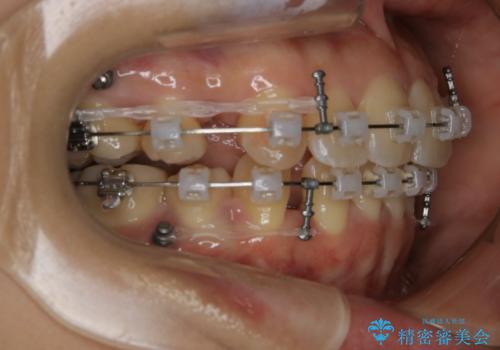

- 矯正装置

- クリア装置

抜歯を行うことで前歯を後ろへ下げるスペースを獲得し、口元の突出感や歯のガタつきを改善していきました。